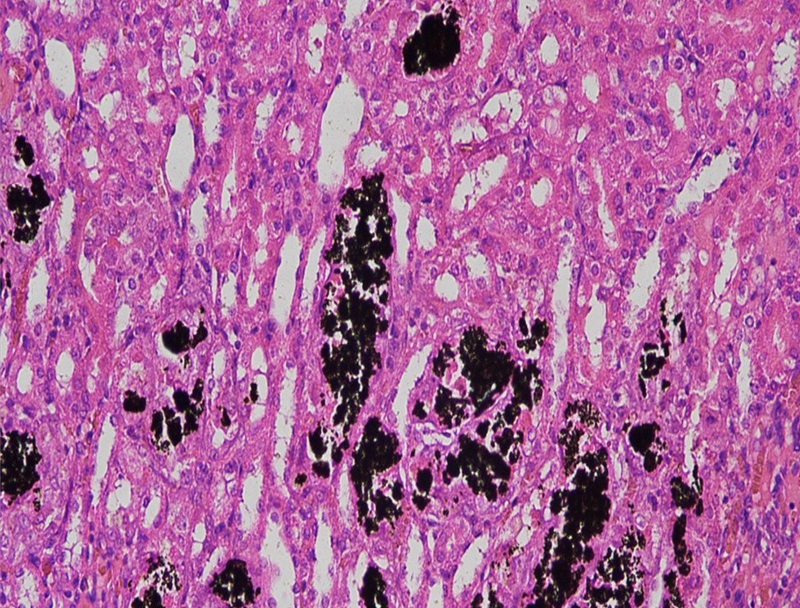

以下是关于 Von Kossa 染色的详细介绍:基本信息定义:Von Kossa 染色是一种特殊的组织学染色技术,用于检测组织和样本中的钙盐沉积,尤其是磷酸钙染色原理:利用银离子与组织中的磷酸钙盐或碳酸钙盐发生反应,在酸性···